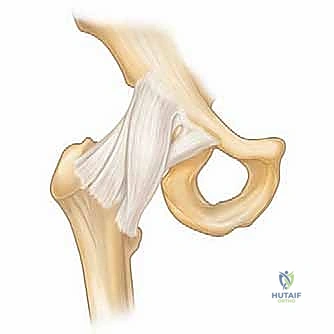

1. الاصطدام الفخذي الحقي (Femoroacetabular Impingement - FAI)

وهي حالة شائعة جداً تحدث عندما تنمو نتوءات عظمية زائدة إما على رأس عظمة الفخذ (Cam) أو على حافة تجويف الحوض (Pincer)، أو كليهما. هذا النمو الزائد يؤدي إلى احتكاك غير طبيعي أثناء الحركة، مما يمزق الشفا الغضروفي ويتلف الغضروف المفصلي.

يقوم الدكتور هطيف باستخدام أدوات دقيقة لنحت هذه العظام الزائدة وإعادة الشكل التشريحي الطبيعي للمفصل.

* إذا كان هناك اصطدام عظمي (FAI)، يتم استخدام جهاز حفر ميكروسكوبي (Shaver/Burr) لنحت العظم الزائد وإعادة تشكيله.